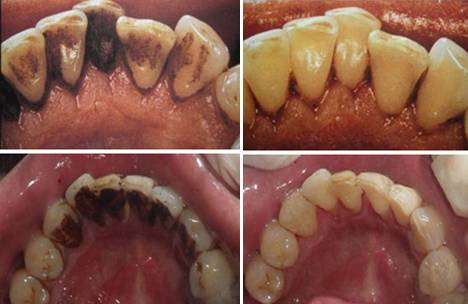

预防龋齿最有效方法:洗牙是预防龋齿的有效方法。牙齿表面会附着牙菌斑和其他沉淀物,如茶渍、烟渍等,容易形成龋齿,也很不美观,通过洗牙可以有效去除这些脏东西。

有效地预防牙周病:人的唾液中溶解了很多矿物质,日积月累的沉积在牙齿上就形成牙结石,也叫牙石。牙结石粘附在牙齿颈部或牙龈下根部,质地坚硬,牙结石藏污纳垢,滋生的各种病菌产生的毒素能刺激牙龈,引起牙龈发炎、红肿、出血,进而引起牙龈萎缩,是造成牙周病的主要原因,还会引起口臭。刷牙等一般方法去除不掉牙结石。只有通过洗牙才能够有效地去除牙结石,保护牙周组织。

洗牙就是指医生通过口腔科专门的器械把我们牙齿表面的牙菌斑,牙结石等清除掉,对于牙周炎和牙龈炎有很好的预防和治疗作用,从而保证我们拥有健康口腔。